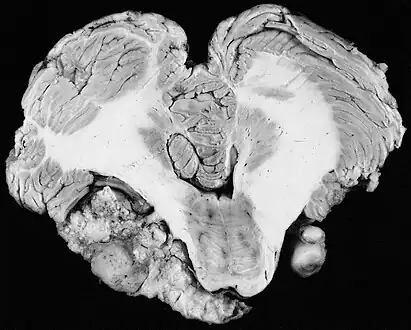

Unilateral vestibular schwannoma -